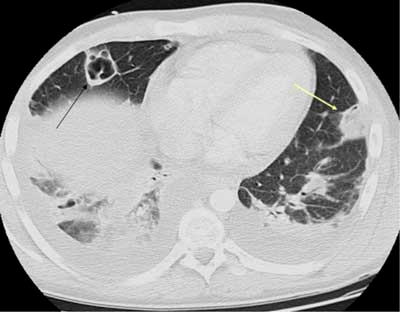

在当地医院就诊,行胸部ct提示:左下肺可见薄壁空洞,并可见气液平,左侧

入院后查肺 ct 示:右肺上叶可见多个类圆形厚壁空洞影,内见气体,最大